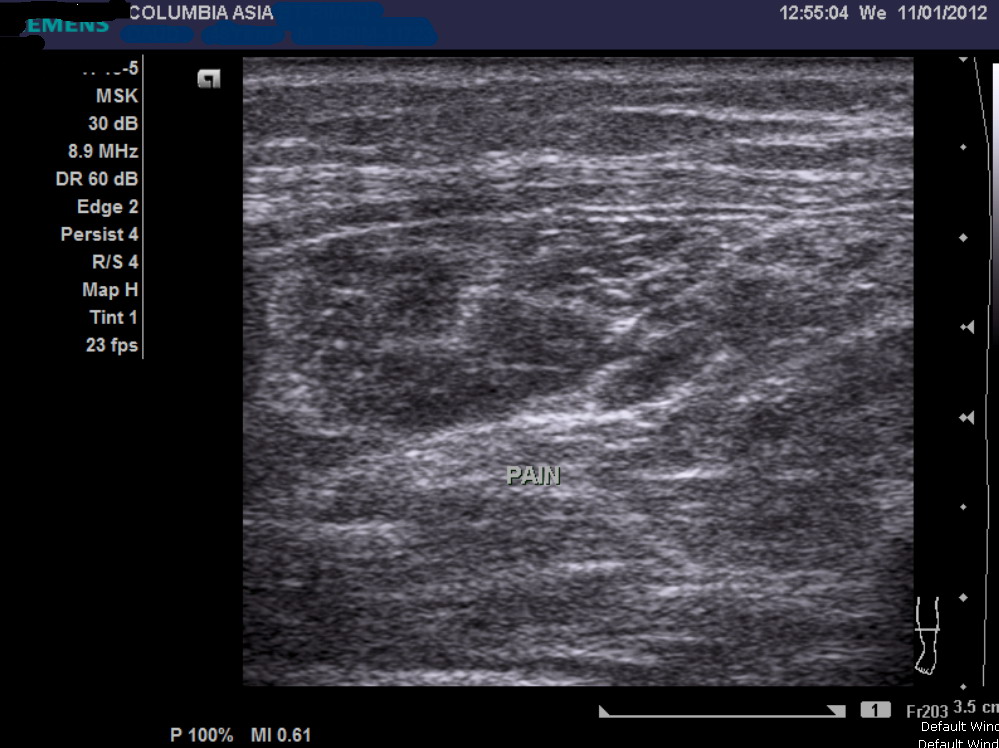

An ultrasound or MRI scan would help in this matter. I promptly sent him across the hallway to see the radiologist requesting for an ultrasound of his calf muscle, failing which we may proceed on to do a MRI scan.

The ultrasound report noted fluid/blood collection within the medial gastrocnemius (calf) muscle, which in the light of the patient’s history, confirmed the patient’s diagnosis:

Gastrocnemius muscle tear (calf tear)